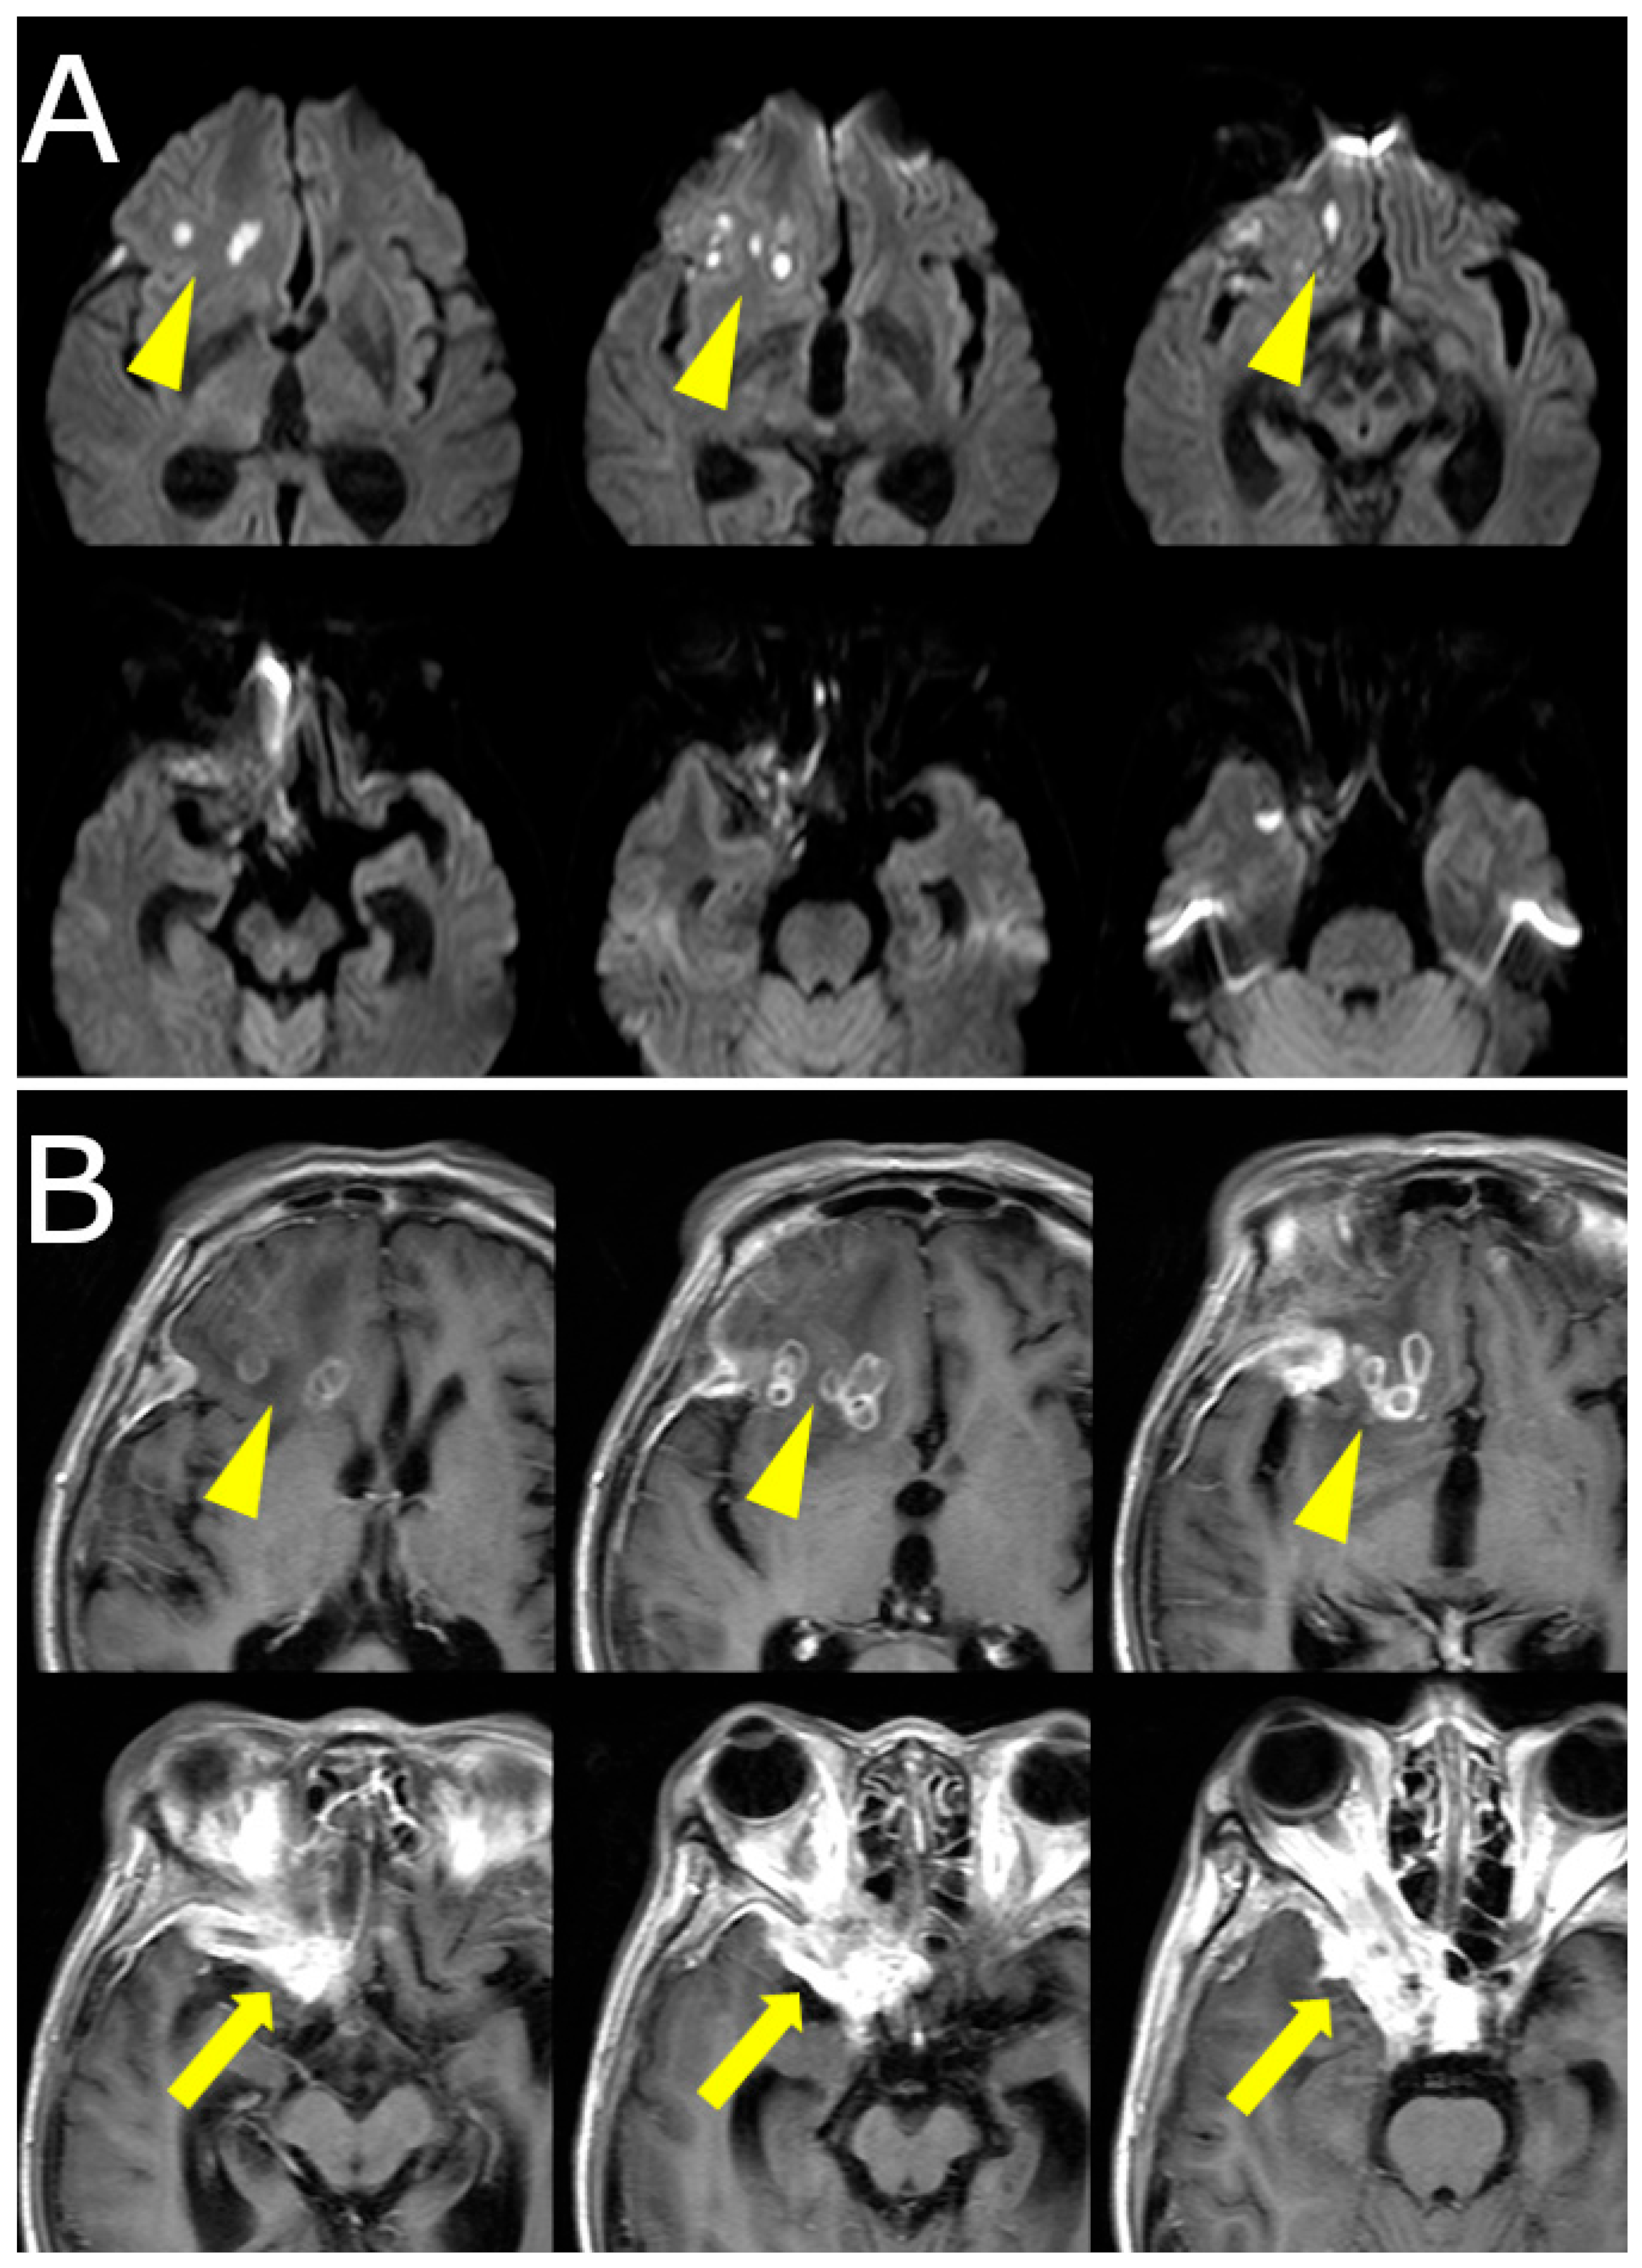

Over the following weeks, her symptoms progressed. She reported increasing difficulty in eye movement, blurred vision in the right eye, and worsening retro-orbital pain. Visual acuity in the right eye decreased to 0.3 (20/60), while the left eye remained unaffected. New findings included proptosis and chemosis without conjunctival injection. Repeat MRI revealed lesion progression into the right cavernous sinus and frontal lobe, with peripheral ring enhancement and central diffusion restriction, suggesting abscess formation. Edema in the right frontal lobe was also observed (Figure 1B, Figure 2).

Figure 2. (A) Diffusion-weighted MRI (DWI) showing restricted diffusion in the right frontal lobe and orbital apex, indicative of abscess formation (yellow arrowheads). (B) Contrast-enhanced T1-weighted MRI demonstrating ring-enhancing lesions in the frontal lobe (arrowheads) and intense enhancement in the orbital apex and cavernous sinus (yellow arrows), consistent with intracranial extension.